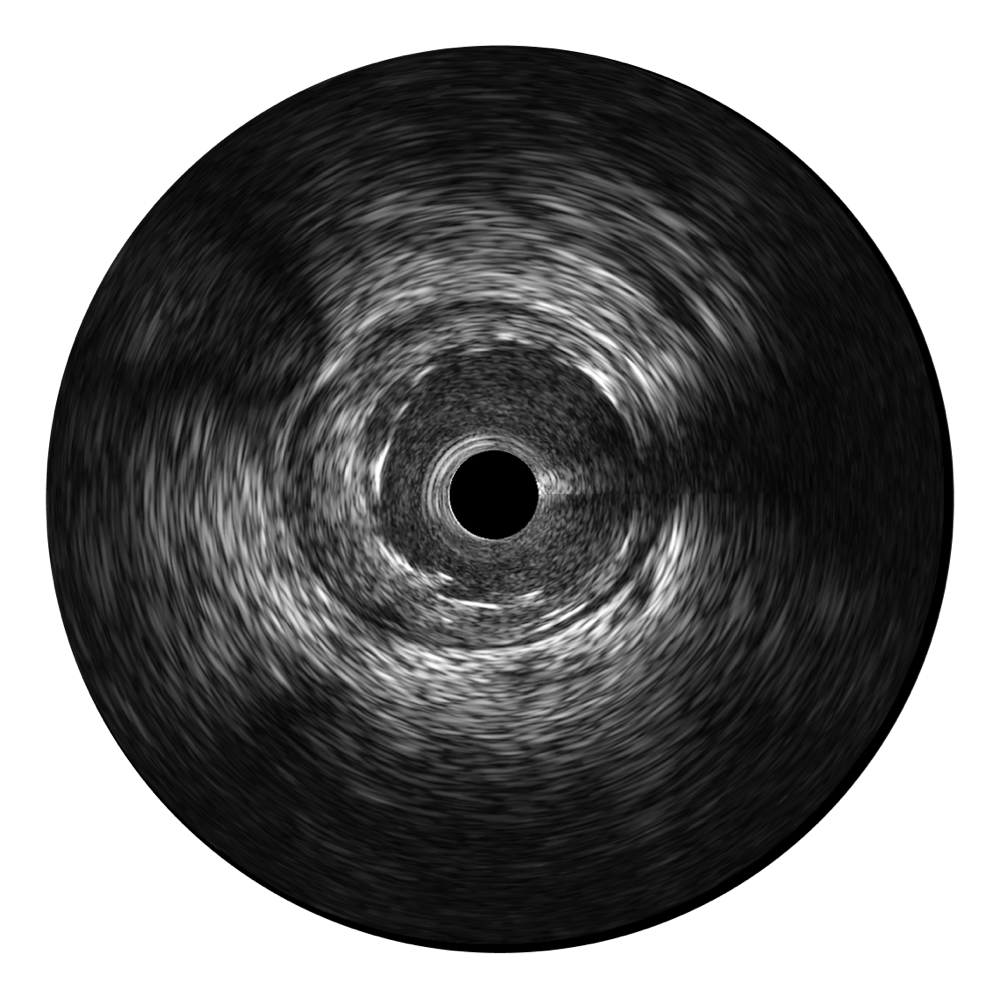

DB中国旗舰官方网站宽频IVUS图像

对比传统IVUS导管成像,DB中国旗舰官方网站宽频IVUS图像的近场支架梁显影更细腻,远场中膜外血管仍清晰可辨,兼顾远中近,兼顾分辨力与穿透深度